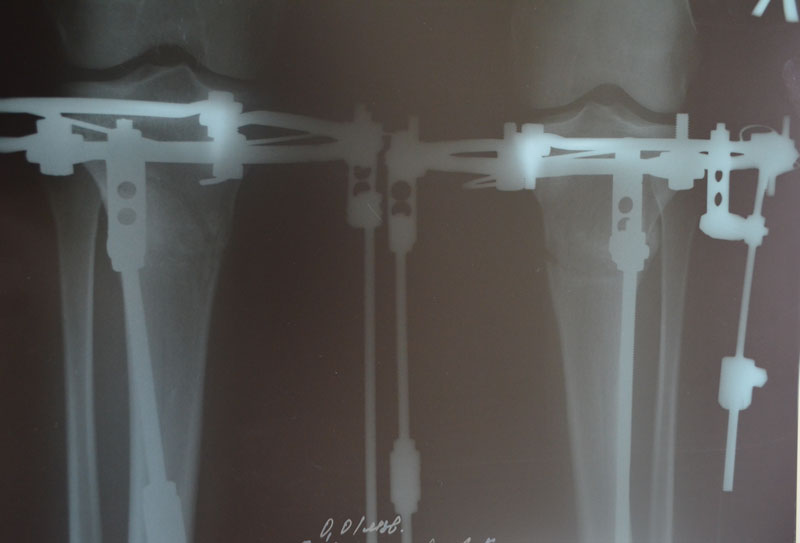

Дата операции 28.01.2014г.

Дата снятия аппаратов 06.05.2014г.

Срок лечения 95 дней.

По рентгену, ось ровнейшая. Правая срослась, а левая... Ходить Вам ещё минимум 3 недели, после делайте ещё рентген и отправляйте по эл. почте. Начинайте принимать препараты кальция и мумиё - его нужно принимать так: развести в 0,5 л. банке 10 таблеток - мумиё, до полного растворения таблеток. После этого, принимать по 1 ст. ложки раствора 3 раза в день. Хранить в холодильнике.